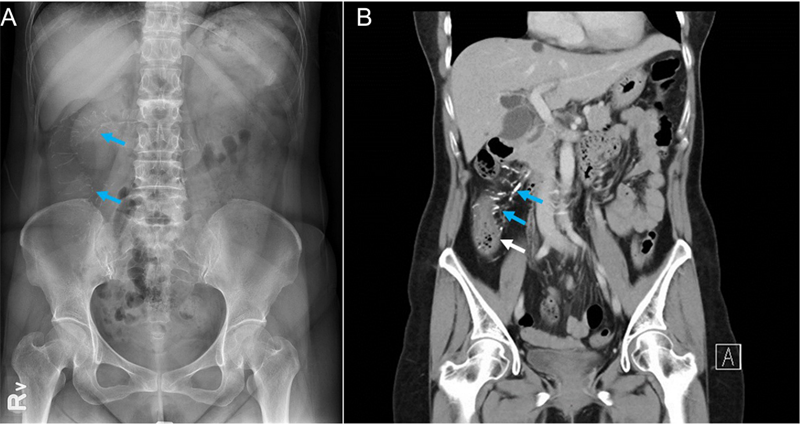

59歲女性,長期反覆出現腹痛、腹瀉及體重下降,在診所、醫院間不斷看診,此次因急性右下腹痛到屏基急診就醫。病患並無發燒,血液檢查亦未顯示白血球增多或發炎指數升高,血液檢驗正常、理學檢查也正常。住院後,醫師在腹部X光片中發現針狀鈣化(Thread-like Calcifications),進一步電腦斷層檢查則顯示右下腹近端升結腸有腫脹及蛇紋狀鈣化(Serpentine Calcifications)。這些影像學特徵確認了腸系膜靜脈硬化的診斷。該疾病推測與腸系膜靜脈內膜的慢性發炎增生導致硬化有關,進而阻礙靜脈血液回流,導致缺血性腸炎。其症狀包括腹痛、腹瀉及體重下降。

腸系膜靜脈硬化是一種少見的疾病,臨床上,主要是以慢性腹痛或腹瀉表現,所以在診斷上經常會被延誤。右側大腸為最常發生之部位,確定診斷主要是依據在腹部X光片上看到腸系膜靜脈針狀鈣化,也因為鈣化影響營養吸收,使得病人營養不良,有過瘦、貧血等問題。此病目前雖無特效藥可治療,但給予正確診斷可以減少病患進行不必要的檢查,大部分病患藥物治療症狀都會獲得改善,僅有極少數重症患者需手術切除缺血壞死的腸段。